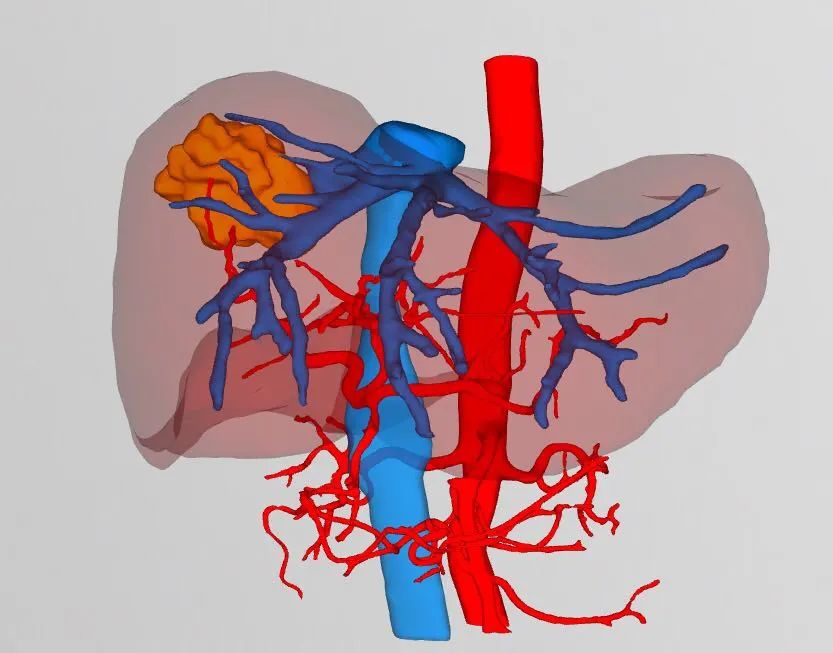

▲术前3D成像评估肿瘤情况(橙色部分为肿瘤)

▲术前3D成像评估肿瘤情况

(黄色部分为肿瘤)